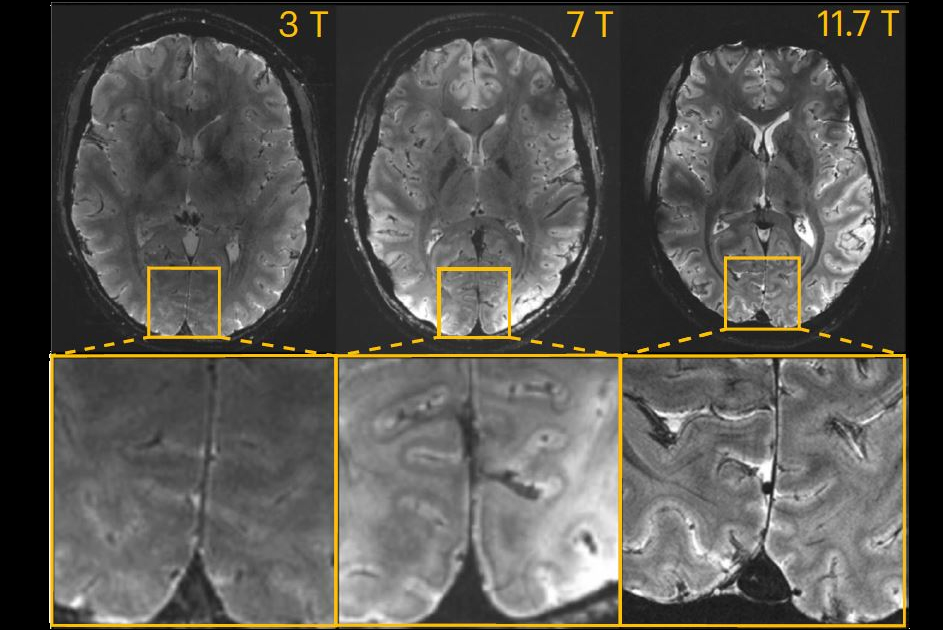

In an MR research session on May 10 in London, Dr. Julien Flament of the Molecular Imaging Research Center in Fontenay-aux-Roses, discussed chemical exchange saturation transfer (CEST) findings in a brain study in rats using 11.7-tesla MR spectroscopy.

CEST is emerging as a new MRI contrast method for molecular imaging. The approach detects small amounts of contrast agent through saturation of fast-exchanging protons, and it benefits particularly from scanning at ultrahigh magnetic fields like 11.7 tesla. Gluco-CEST uses natural D-glucose as a contrast agent instead of conventional contrast agents, and thus provides data on glucose delivery, uptake, and metabolism in the brain.

Imaging data were acquired using a horizontal 11.7-tesla MR spectroscopy Bruker magnet. Specifically, diffusion-weighted gluco-CEST data were acquired in a 2.5 x 2.5 x 2.5-mm3 voxel located in the left striatum of the rats over two hours before, during, and after injection.